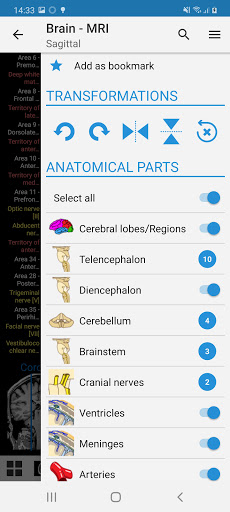

- يتميز وضع الدبابيس بسلوك جديد يسمح لك باتباع بنية تشريحية بسهولة أكبر

- يمكنك الآن تحديد حجم الخط الذي تفضله يدويًا لتسميات الهياكل التشريحية (في وضع الملصقات)

- ضمن عرض التفاصيل للبنية التشريحية ، يشير الدبوس الآن إلى البنية ذات الصلة في جميع الصور الحالية

انقر أيضًا مباشرة على الصورة للانتقال إلى الصورة المعروضة في تلك الوحدة